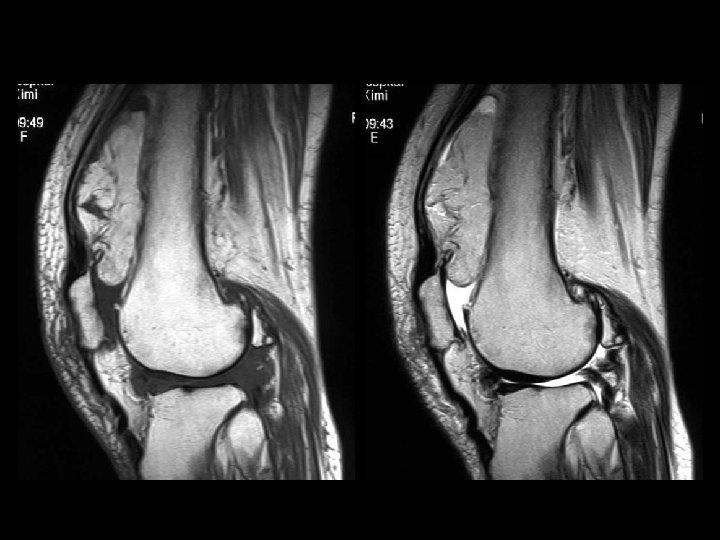

Lipoma arborescens • Findings: – Fatty lesion within the suprapatellar pouch • ddx: – NONE! – This is an Aunt Minnie!